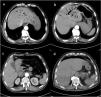

During hospitalization, a 79-year-old male suddenly suffered abdominal pain, nausea, vomiting, and cold sweating after using the toilet on the 5th day after lumbar disc surgery. A point-of-care ultrasound displayed a “shred sign” and “pseudo-B lines” within the liver (Video 1 in Supplementary material), which was analogous to the echo profile of lung consolidation, indicating suspected intrahepatic gas. Subsequently, an abdominal computed tomographic angiography confirmed extensive gas accumulation in the portal vein (Fig. 1a–c red arrow), multiple intestinal gases, retroperitoneal effusion, and normal mesenteric artery imaging. The patient received an emergency laparotomy, during which retroperitoneal effusion was drained. Afterward, circulatory shock was quickly corrected, and the portal vein gas accumulation disappeared 48 h later (Fig. 1d).